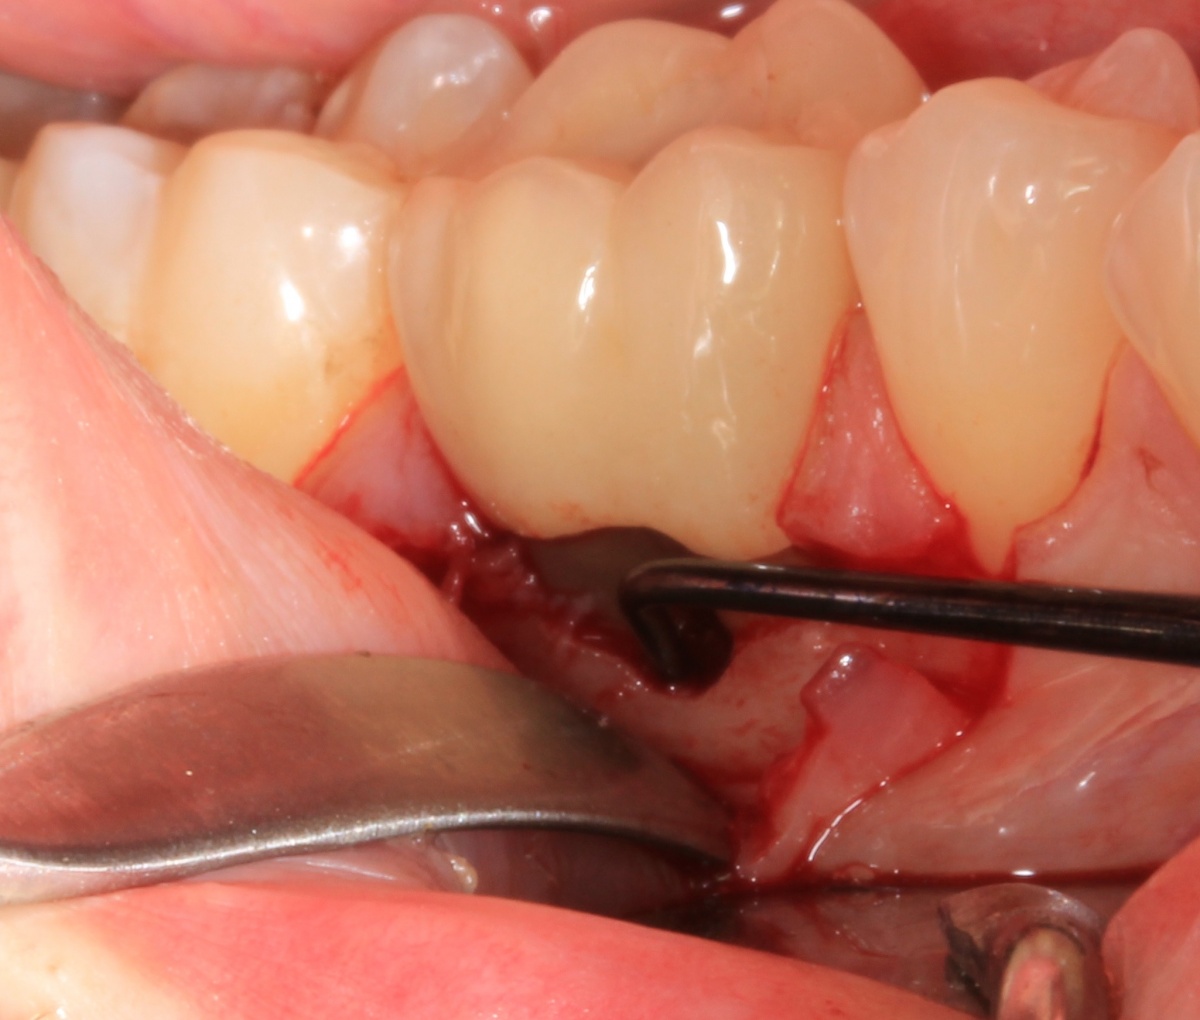

Durch eine Vielzahl von Studien konnte belegt werden, dass die Versorgung mit implantatgetragenem Zahnersatz eine bewährte Behandlungsoption darstellt. Gleichwohl zeigen viele Studien jedoch, dass – wie bei allen Therapiemaßnahmen auch – Komplikationen auftreten können. Diese haben im Allgemeinen biologische oder technische Ursachen. Als häufigste biologische Komplikation findet man die Mucositis (Abb. 1), die Entzündung der periimplantären Gewebe ohne Beteiligung des Alveolarknochens. Nach aktuellen Studien weisen ca. 30 % aller Implantate nach fünf Jahren eine Mucositis auf. Kommt es darüber hinaus zu einer Beteiligung des Alveolarknochens, liegt eine Periimplantitis vor (Abb. 2). Sie tritt nach fünf Jahren bei etwa 10 % der inkorporierten Implantate auf und ist durch den Verlust des periimplantären Alveolarknochens gekennzeichnet. Die Periimplantitis kann, je nach Schweregrad, zum kompletten Implantatverlust führen. Bei einem strategisch wichtigen Implantat kann daraus der Verlust der gesamten prothetischen Versorgung resultieren und eine operativ sowie finanziell aufwendige Neuversorgung erforderlich werden (Abb. 3).